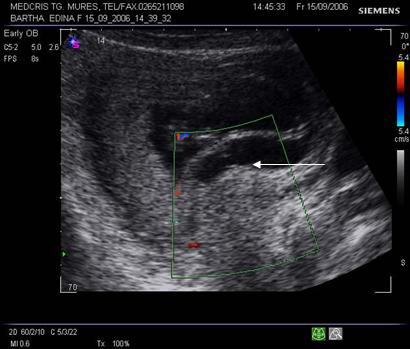

Fig nr. 70 Aceeasi sarcina ca in figura precedenta,la eco Doppler se observa lipsa fluxului sangvin in hematomul subchorial ( sageata)

Fig nr. 71. Decolare de pol inferior recenta, la o pacienta cu metroragie si prezenta fluxului sangvin la eco Doppler ( sageata )